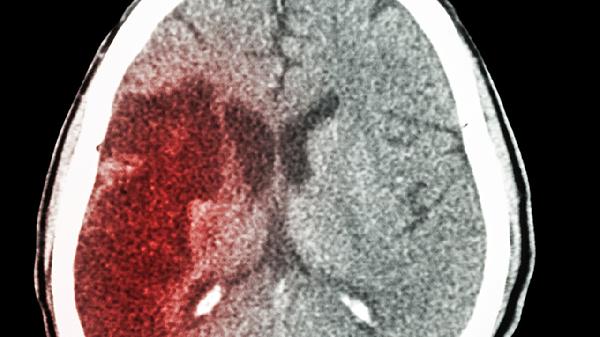

脑出血的部位主要有基底节区、丘脑、脑叶、小脑和脑干等。脑出血是指非外伤性脑实质内血管破裂引起的出血,常见于高血压合并细小动脉硬化患者。

基底节区是脑出血最常见的部位,约占所有脑出血的50%-70%。该区域由豆状核、尾状核等结构组成,出血多与高血压导致的小动脉病变有关。基底节区出血可能表现为对侧肢体偏瘫、感觉障碍和偏盲等症状。治疗需控制血压,必要时可考虑血肿清除术。